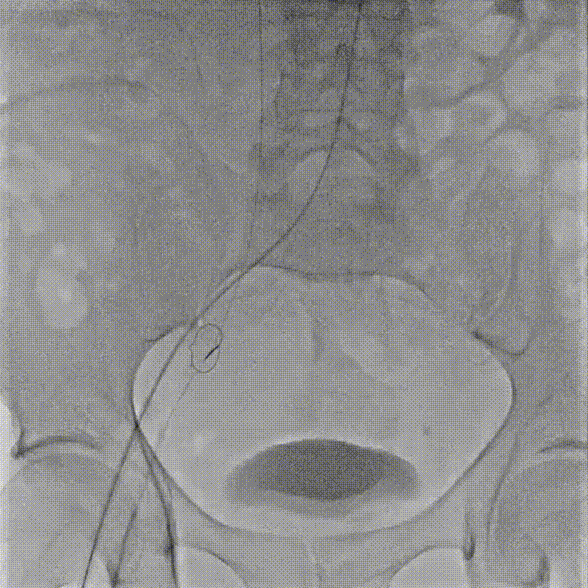

术中操作